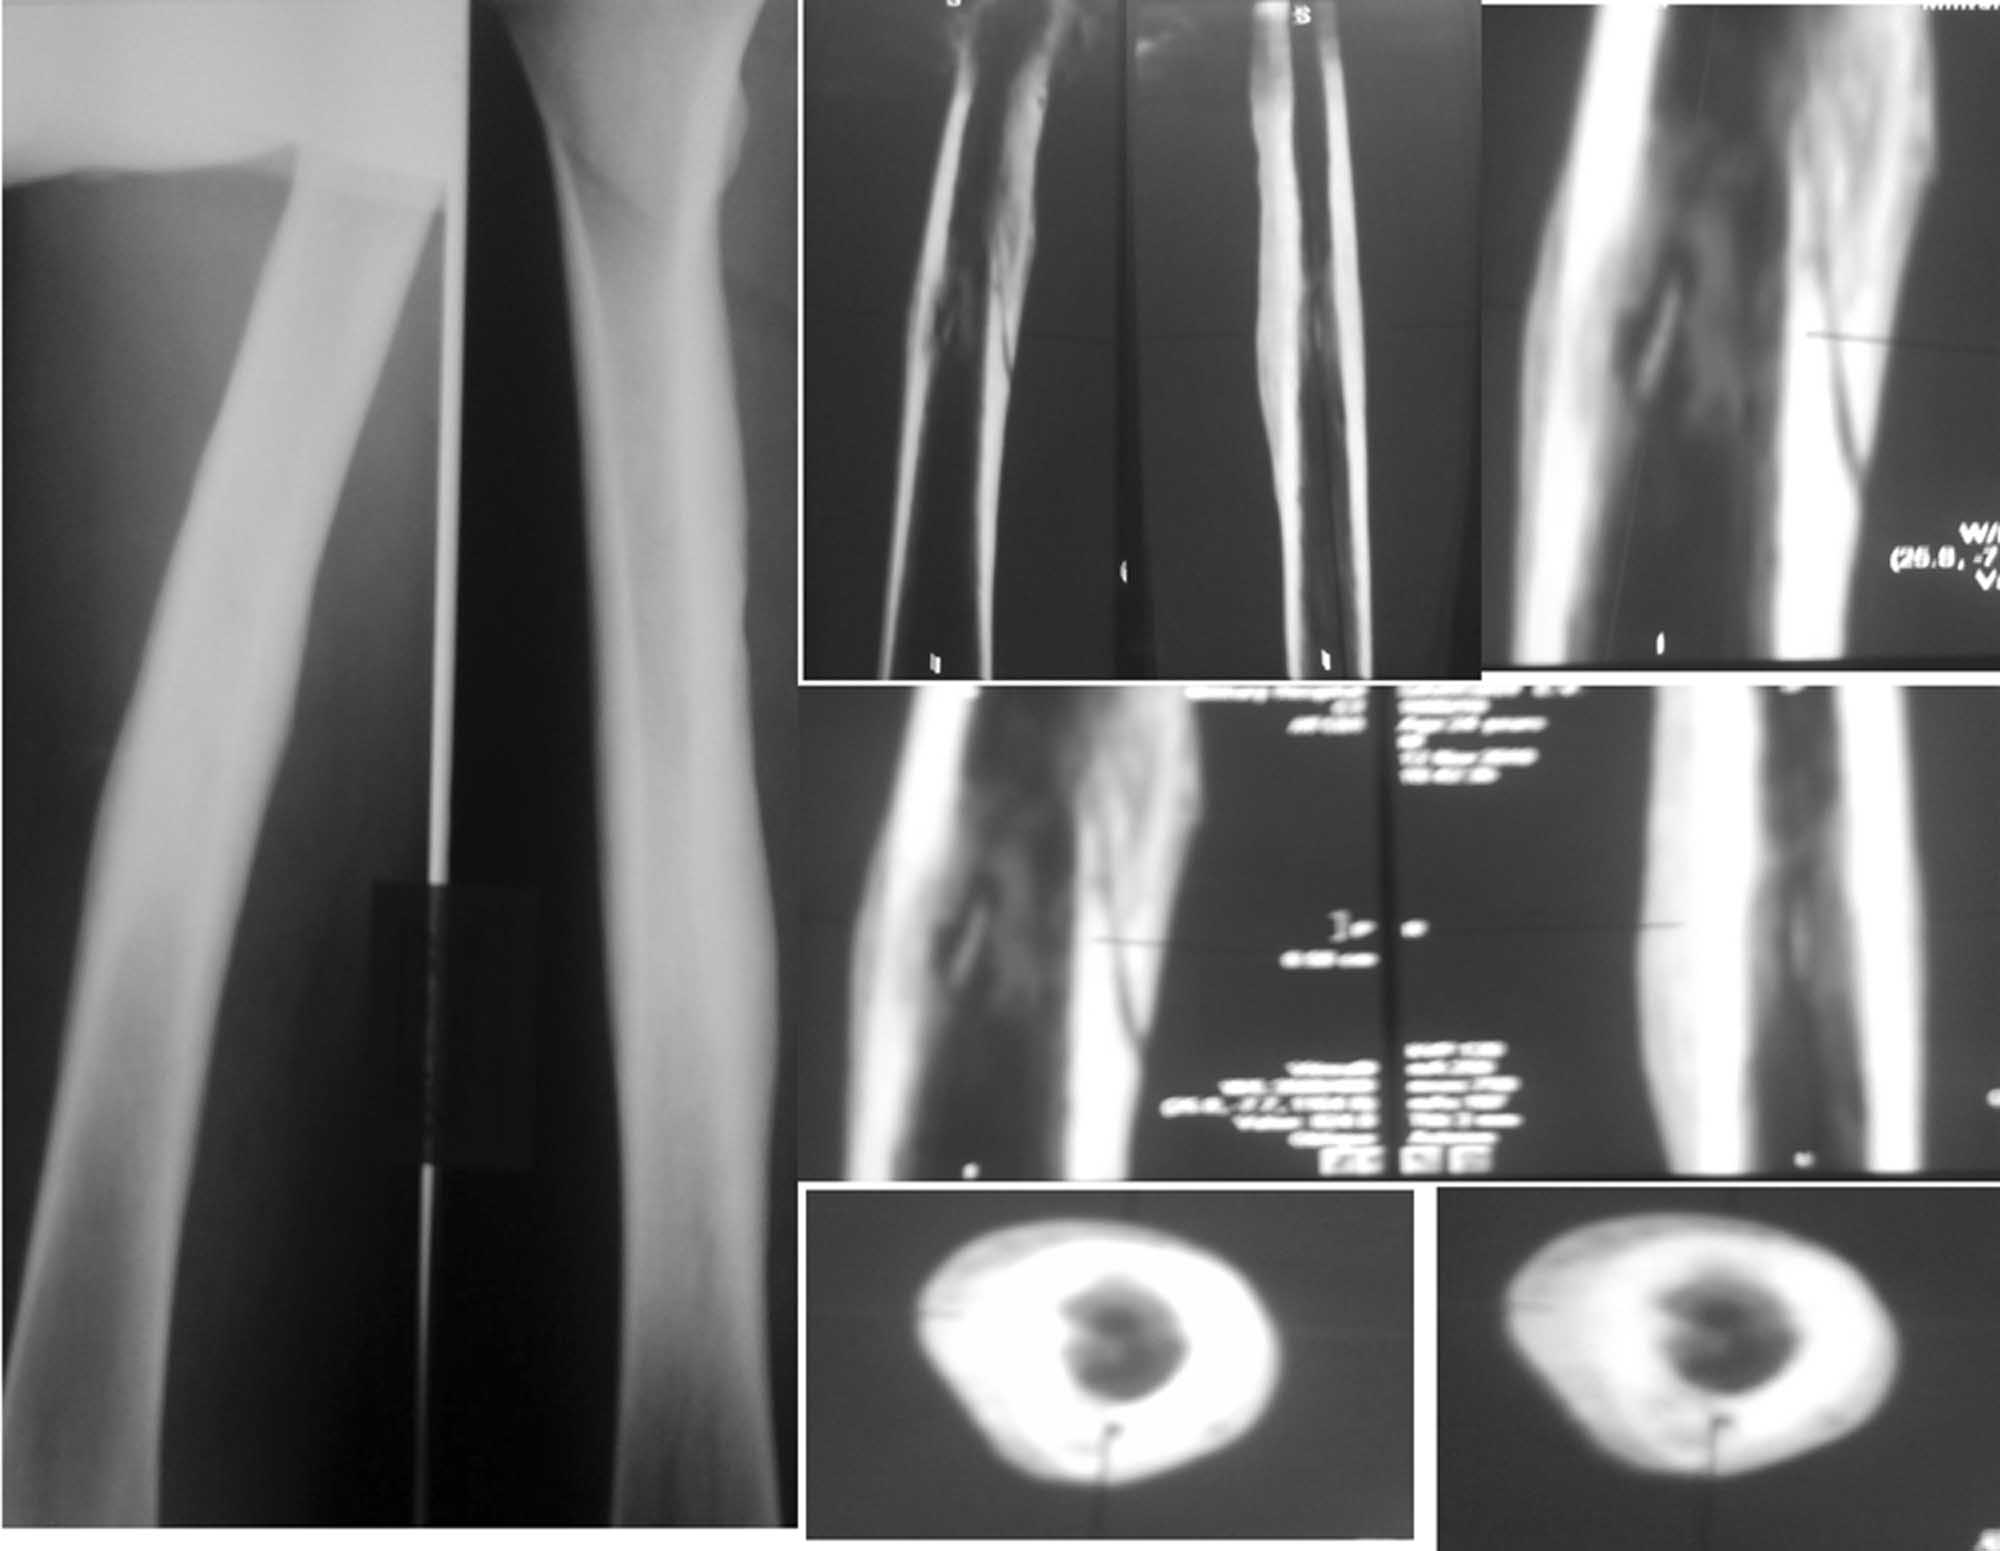

Случай ╚ вялотекущего ╩ гематогенного остеомиелита у молодого пациента

Пациенту 24 года. Беспокоят умеренные боли в области нижней трети правого бедра при

нагрузках и ограничение сгибания правого коленного сустава. В покое, в т.ч. ночью, болей

нет. 2 года назад без видимой причины появились боли и припухлость в нижней трети правого

бедра. Был госпитализирован в отделение гнойной хирургии с диагнозом ╚ Воспалительный

инфильтрат ╩ . Рентгенограммы бедра в тот период патологии не выявили. На фоне а/б терапии

цефазолином инфильтрат разрешился полностью. Последующие 2 года ничего не беспокоило.

Около 2 недель назад появились боли и припухлость в нижней трети правого бедра, вновь без

видимой причины. На рентгенограммах бедра выявлены выраженная периостальная реакция, на

КТ признаки хронического гематогенного остеомиелита. Объективно: внешне мягкие ткани

бедра не изменены, следов от свищей нет, умеренно болезненна область нижней трети правого

бедра по медиальной поверхности, без изменения кожной температуры, признаков

инфильтрации и флюктуации. Ограничено сгибание в правом коленном суставе до 90 гр из-за

болей. Лабораторные данные без особенностей за исключением СОЭ 25 мм в час, уровень СRP в 2

раза выше нормы. УЗИ мягких тканей изменения эхоструктуры тканей не выявило. Выполнение МРТ

и сцинтиграфии не возможно в связи с отказом пациента. Вопросы: необходимо ли

дообследование? Целесообразно ли консервативное лечение с учетом выявленной на КТ

секвестральной полости? Возможные варианты оперативного лечения?